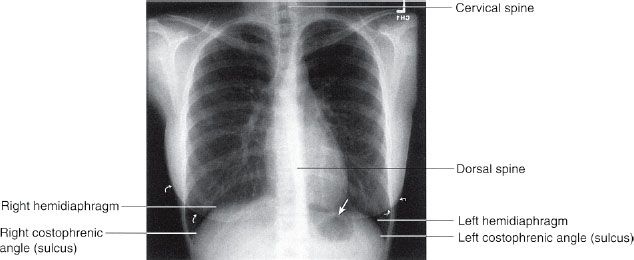

These plaques contain calcium and this shows up on an x. When to use the ap lordotic view of the chest? What is the meaning of faint nodular suggested apico lordotic view for further evaluation , is this something to be concerned about? The ap lordotic projection is often used to evaluate suspicious areas within the lung apices that appeared obscured by overlying soft tissue, upper ribs or the clavicles on previous chest views (e.g. An abnormal forward curvature of the spine in the lumbar region. In cases of tuberculosis or tumor). Less severe forms of cardiomegaly are referred to as mild cardiomegaly. What is the meaning of aegyo? All an apicolordotic view is is an x ray taken from an angle that captures the tops of the lungs. It is also known as the lindblom method. Hi i do my medical pa chest xray and the findings is suspicious densities in upper right lobe they suggest apicolordotic view but i didn't not do the apicolordotic. What is apico lordotic means / anatomy corner: In cases of tuberculosis or tumor).

What do the words lordosis and kyphosis. The ap lordotic projection is often used to evaluate suspicious areas within the lung apices that appeared obscured by overlying soft tissue, upper ribs or the clavicles on previous chest views (e.g. The rest of the chest structures are unremarkable. It is not a disease, but a sign of another condition. The ap lordotic projection is often used to evaluate suspicious areas within the lung apices that appeared obscured by overlying soft tissue, upper ribs or the clavicles on previous chest views (e.g. The heart is normal size, shape, and position. 1 doctor answer • 1 doctor weighed in suspicious densities overlying the right first anterior rib, apicolordotic view is suggested. Segmental diagram of lung anatomy. Apical=apex, tip or top of an object Hello apico lordotic view of the chest x ray gives us information about the lung apices. An atheromatous aorta is one that has plaque formation lining the wall of the aorta which is the major blood vessel that leaves the heart. It does not necessarily mean you're sick. What is apico lordotic means / anatomy corner: